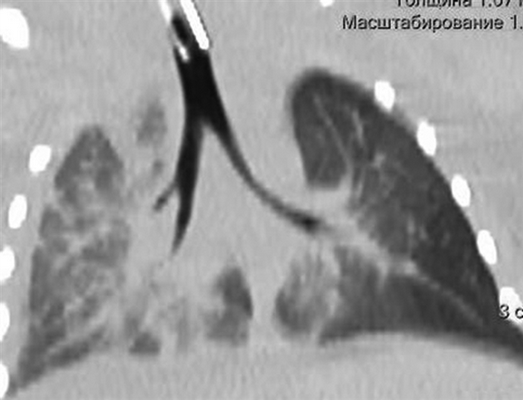

Девочке 2-х суток жизни выполнена МСКТ в условиях медикаментозной седации с проведением проспективной ЭКГ-синхронизации, болюсного внутривенного контрастирования (в/в) препаратом Визипак 270 в объеме 6 мл в периферическую вену правой нижней конечности. Сканирование осуществлено на аппарате Philips Ingenity 128, kv 80, mas 350, протяженность сканирования 250 мм. Выполнено обзорное сканирование грудной клетки и брюшной полости до контрастного усиления, по результатам которого определяется диффузная неравномерность пневматизации легочной паренхимы, с наличием участков ателектазированной легочной ткани в верхних и нижних долях легких с обеих сторон, в обеих плевральных полостях определяется умеренное количество выпота (рис. 3). Сердце визуализировано вне грудной полости (рис. 4). В грыжевом мешке определяется фрагмент паренхиматозного органа брюшной полости, по нативным денситометрических показателям идентичный паренхиме печени (50HU), как показано на рисунке 5.

Рис. 3. Мультиспиральная компьютерная томография, мультипланарная реконструкция (MPR) легких в корональной проекции, в просвете трахеи интубационная трубка, пневматизация легких диффузно неравномерная с наличием участков ателектазированной легочной ткани

Рис. 4. Мультиспиральная компьютерная томография (МСКТ) легких, аксиальная проекция, патологический выпот в обеих плевральных полостях, эктопия сердца на переднюю грудную стенку

Рис. 5. МСКТ брюшной полости, аксиальная проекция, визуализирован грыжевой мешок, содержащий правую долю печени

После в/в контрастрования сканирование произведено в двух направлениях — каудокраниальном и краниокаудальном с целью визуализации анатомии сердца, определения сопутствующих пороков. В первую очередь требовалось уточнение анатомии камер сердца. По результатам исследования визуализированы полости правого и левого желудочков (ПЖ и ЛЖ), разделенные межжелудочковой перегородкой, с наличием дефекта в подклапанном отделе.